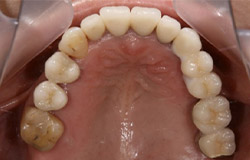

インプラントで噛み合わせの再構成を伴った症例。

治療後のメンテナンスを行わないと

周囲炎になるリスクあり。